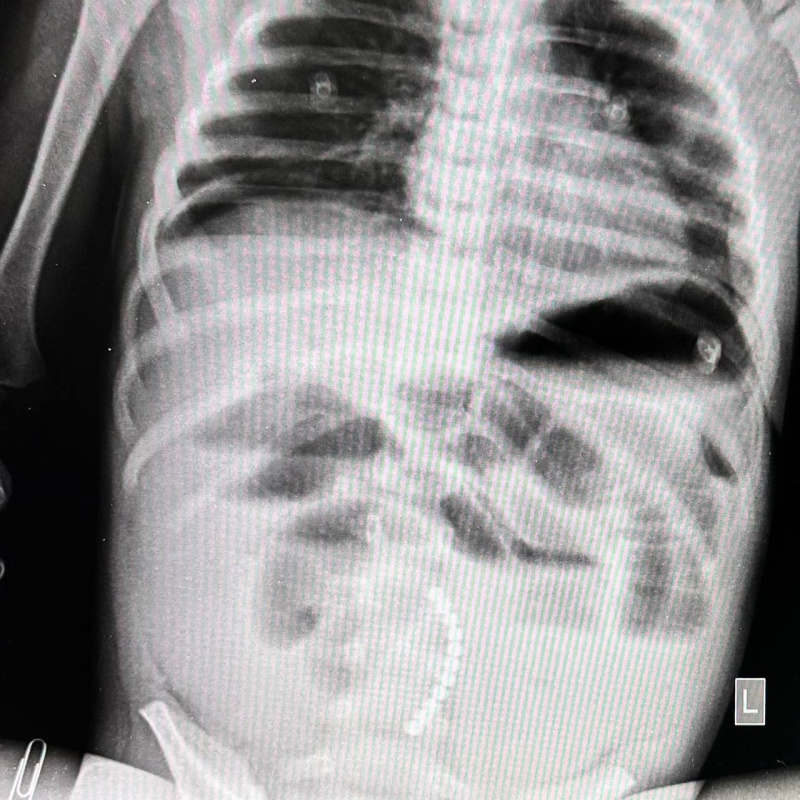

И вновь необычные находки врачей детской больницы

С коллегами были удивлены, как ребенку удалось проглотить такую большую деталь, в диаметре предмет был более 3-х сантиметров

Неожиданная находка в практике врачей детской больницы

Ребенка госпитализировали в хирургическое отделение, с целью планового обследования и уточнения состояния